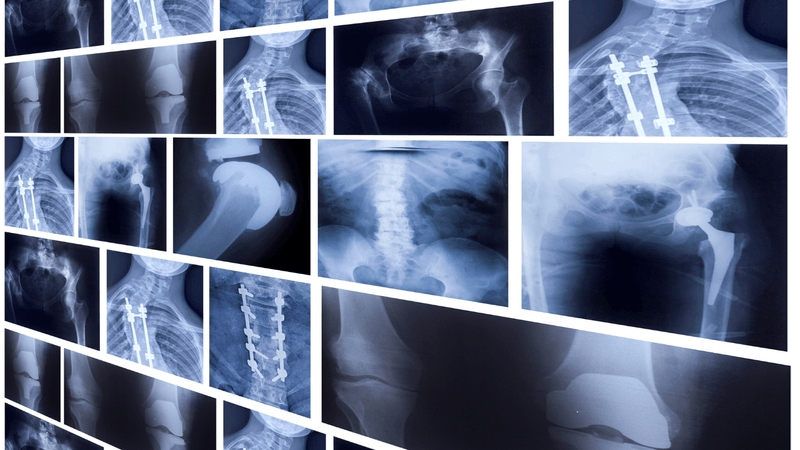

X-rays, often synonymous with detecting fractures and bone injuries, are just one aspect of diagnostic imaging technology. In reality, X-rays are incredibly versatile and can be used to visualize a variety of structures within the body, including bones, soft tissues, and internal organs. From diagnosing respiratory conditions to detecting tumors and evaluating joint health, X-rays play a crucial role in diagnosing and monitoring a wide range of medical conditions.

One of the key advantages of X-ray imaging is its ability to provide detailed and precise images of internal structures with minimal invasiveness. By passing electromagnetic radiation through the body, X-ray machines generate high-resolution images that allow healthcare providers to visualize abnormalities, identify injuries, and guide treatment decisions. Whether it's assessing the severity of a lung infection or evaluating the progression of arthritis, X-rays offer valuable diagnostic information that can inform patient care and improve outcomes.